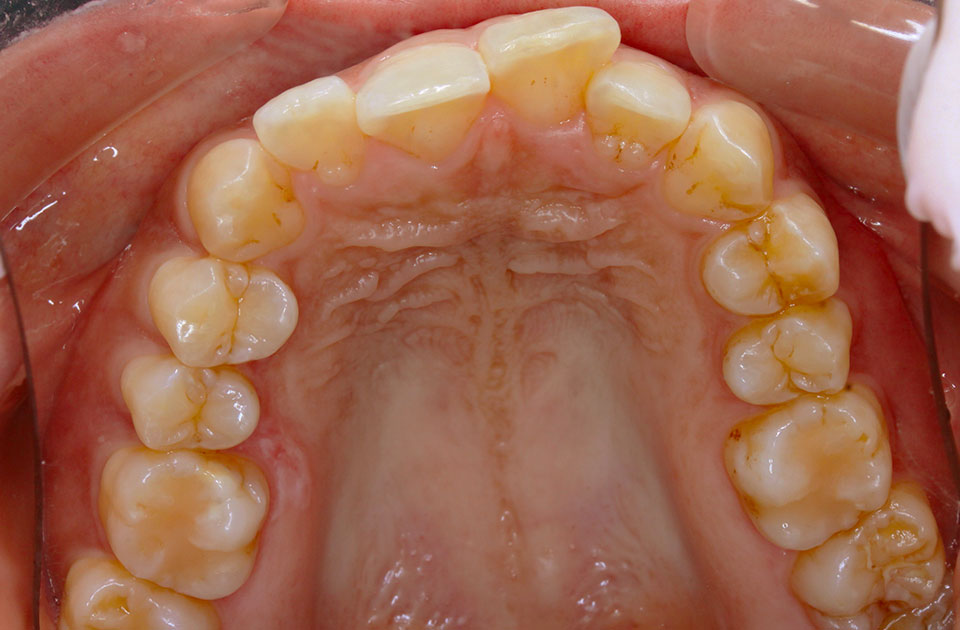

矯正前 上顎

矯正後 上顎